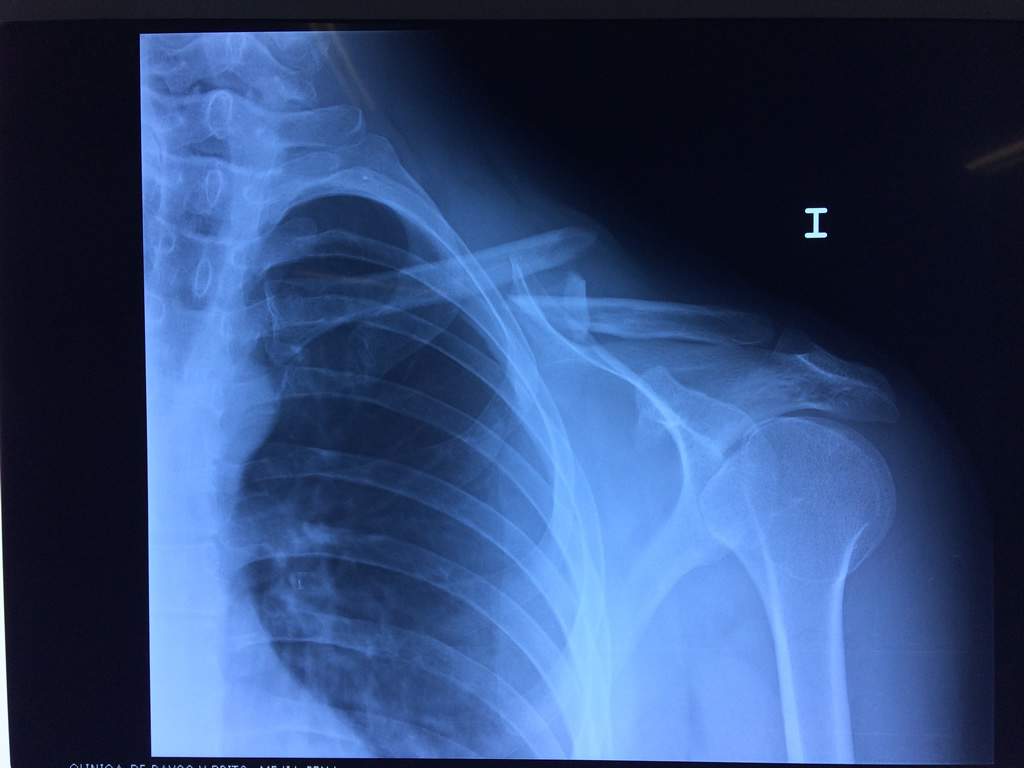

Fémur - Clavícula

La clavícula es un hueso largo, con forma de "S" itálica, situado en la parte anterosuperior del tórax. Junto con la escápula forman la cintura escapular. Se puede palpar por toda su longitud y se extiende del esternón al acromion de la escápula, siguiendo una dirección oblicua lateral y posterior.

Se considera el único medio de unión entre el miembro superior y el tórax. A pesar de su aspecto, similar al de un hueso largo, posee una estructura semejante a la de un hueso plano, ya que carece de epífisis y de diáfisis, lo que la harían entrar dentro de la clasificación de hueso largo. Carece de un canal medular propiamente dicho.